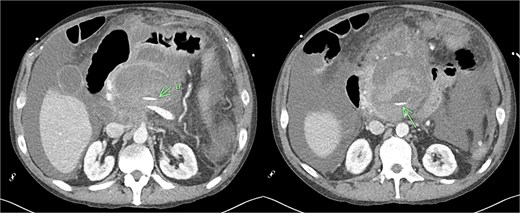

Recovery was complicated by progressive necrotising pancreatitis with evidence of active bleeding into a peripancreatic collection (Fig. 7) and a pseudoaneurysm arising from a branch of the superior mesenteric artery (SMA) associated with haemoperitoneum (Fig. 8).

CT angiogram of abdomen axial and coronal view; small pseudoaneurysm arises from a branch of the SMA (arrow). Large haematoma in the head of the pancreas and diffuse haemoperitoneum throughout the abdomen/pelvis.